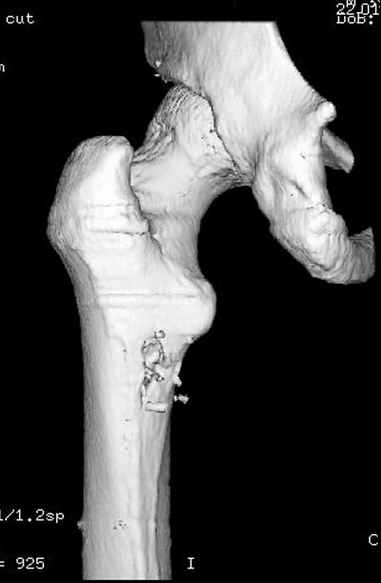

Учитывая, что больной получил травму не во время визита в церковь, и он является одним из представителем 40 миллионного “outstanding itizen”, без медицинской страховки, без работы в свои 39 лет, и без надлежающей ортопедической дисциплины у которого отсутсвует страх стрессового перелома, было рекомендовано оперативное лечение: профилактическое антеградное интрамедуллярное штифтование.

Выглядит агрессивно, и обычно госпиталь, беря финансовые расходы, остается в убытке, но мы всё же посчитали, что издержки от штифтования намного меньше, чем возможные финансовые и моральные издержки лечения таких больных, но с осложнением.

Методика штифтования при отсутствии большой зоны перелома как при онкологических профилактических штифтованиях, расверливание интрамедуллярного канала проводим с предварительным наложением дополнительного дренажного отверстия в дистальном отделе бедра (в данном случаи в канале оставили 6.5 мм канюлированный шуруп), иначе при создании давления в канале во время сверления имеется опасность эмболизации легочной артерии тромбом.